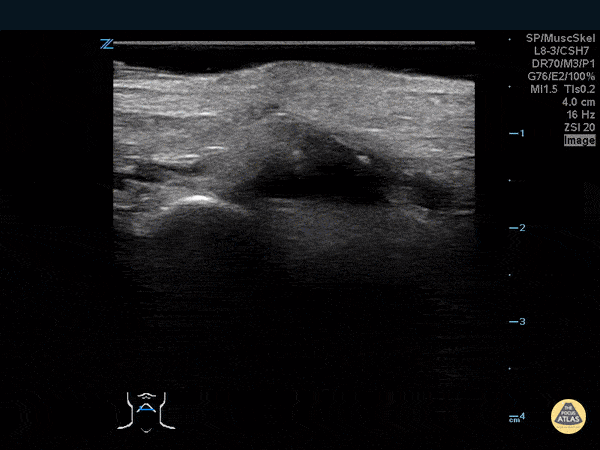

Musculoskeletal - Thumb Fracture

30 year-old male ED resident who injured his thumb at some point while playing football versus the attendings in the annual flag football game. He figured the thumb had merely been sprained, and he kept playing in the game (and scoring touchdowns) while the residents dominated. Two days later the swelling/ecchymoses seemed to worsen, he used the linear transducer in a water bath to diagnose a fracture of the base of the 1st metacarpal. An x-ray confirmed the diagnosis, and he underwent percutaneous pinning in the operation room the following week. Dr. Stephen Alerhand, Mt Sinai Hospital, NYC